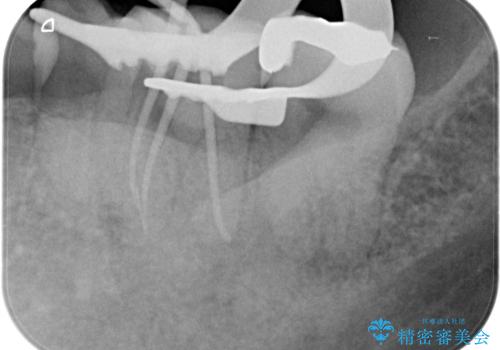

根管治療から被せ物の治療

- 噛んだ時の痛みを主訴に当院受診されました。

根管治療を行なったのち、症状改善を認めオールセラミッククラウンにて修復治療を行なっております。

┌7は今回の治療後打診(-)、正常歯髄へ診断のもと経過観察を行なっております。